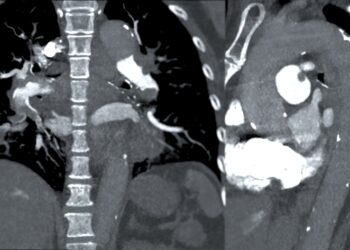

Skaityti daugiauDetailsBendrasis tulžies latakas – tai siaura, vamzdelio formos struktūra, atsirandanti susijungus bendram kepenų latakui su cistiniu tulžies pūslės lataku. Pagrindinė...